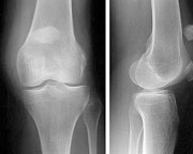

Fracturas de rótula

Las fracturas de rótula representan el 1% de todas las fracturas del esqueleto. Son doblemente más frecuentes en la mujer que en el hombre y, sobre todo, entre la tercera y quinta década de la vida. El impactode la rodilla en flexión sobre el suelo suele ser el mecanismo de producción habitual aunque en otras ocasiones se debe a una contracción brusca del cuádriceps. El hematoma y la imposibilidad para mover la rodilla hacen sospechar el diagnóstico que se confirma radiológicamente con una proyección lateral. El tratamiento de las fracturas de rótula se ha beneficiado de los avances en traumatología mínimamente invasiva pudiendo ser resueltas a través de pequeñas incisiones en la piel gracias a la ayuda de la artroscopia.